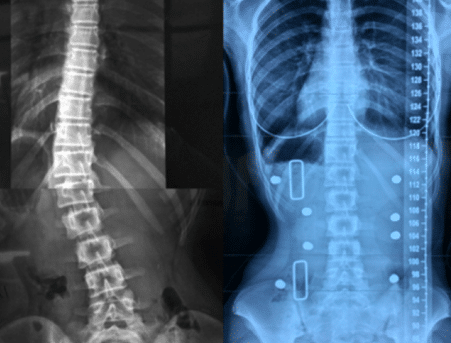

2. الأشعة بعد الخروج من الحزام (FOB-XR)

هي الأشعة التي تُؤخذ بعد فترة قصيرة من خلع الحزام خلال اليوم، وتُعتبر أكثر واقعية لأنها تُظهر:

- قدرة العمود الفقري على الحفاظ على التصحيح

- قوة العضلات

- التوازن العصبي العضلي

وهنا تظهر أهمية كبيرة، لأن الهدف الحقيقي من العلاج ليس فقط “تصحيح مؤقت”، بل الحفاظ على التحسن بدون دعم خارجي.